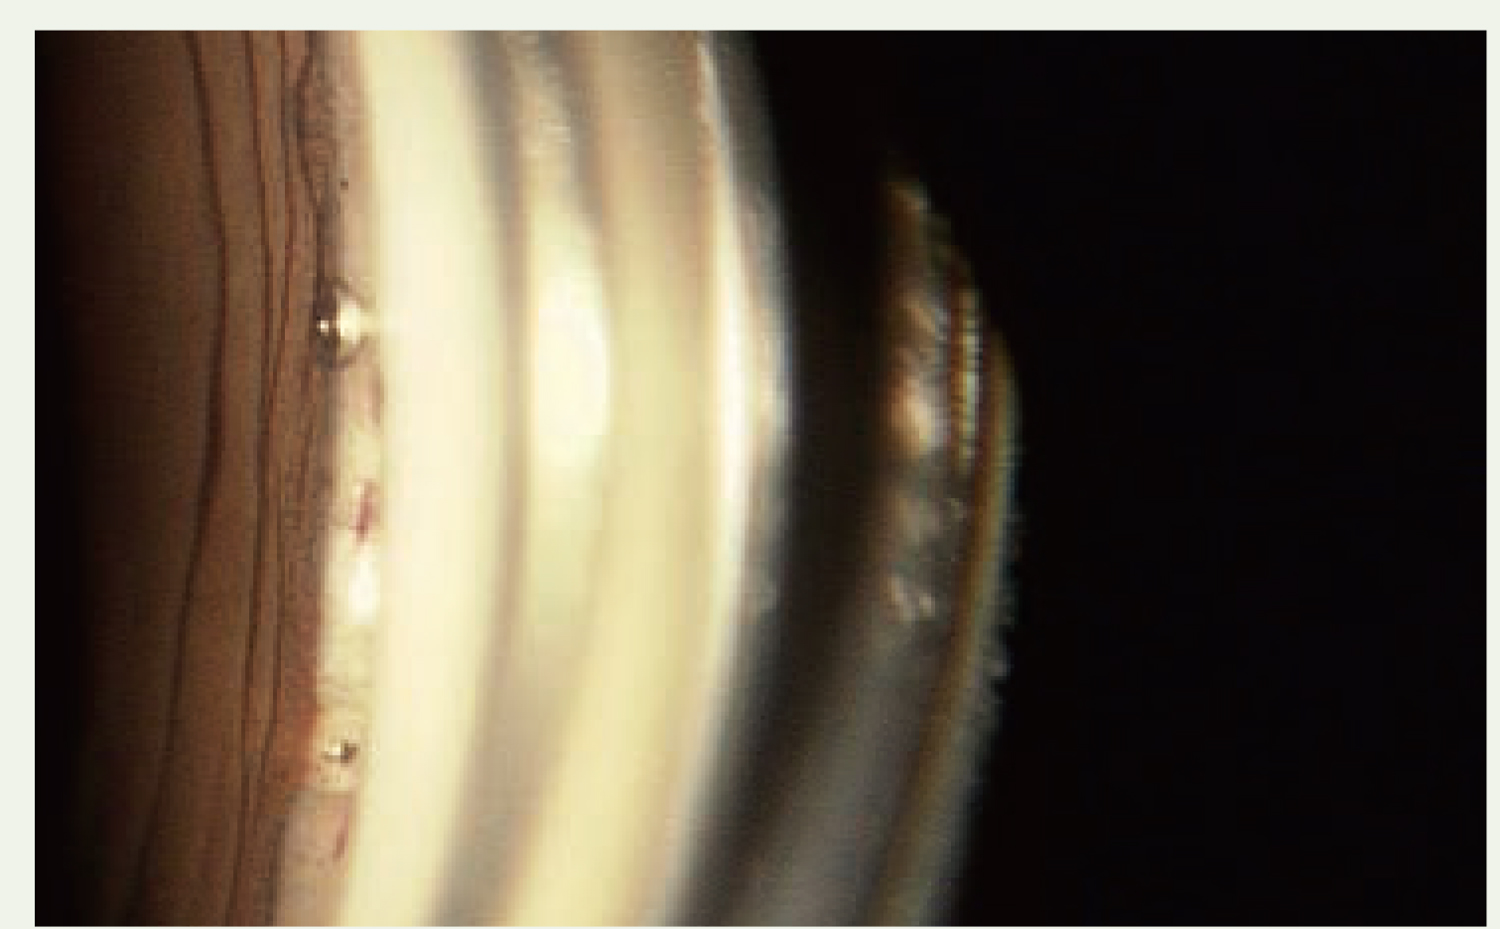

| アーメド緑内障バルブのチューブ先端を毛様溝に留置している症例。 角膜内皮細胞への影響を考慮して、無硝子体眼・有水晶体眼以外には、この方法で施行することが増えました。 | ||